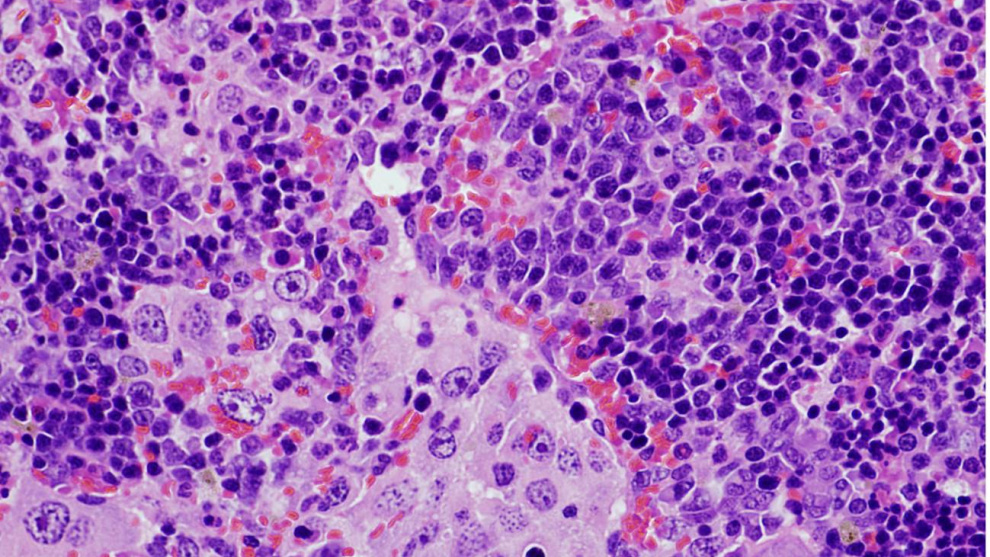

Una alteración genética que afecta al gen VAV1 desempeña un importante papel en tumores derivados de los linfocitos T (linfomas) y el cáncer de pulmón, dos tipos de cánceres que se caracterizan por tener tasas de supervivencia muy bajas. Esta es la principal conclusión de un estudio liderado por el Consejo Superior de Investigaciones Científicas (CSIC).

"Por un lado, hemos demostrado que la alteración genética en VAV1 no es suficiente para inducir la formación de tumores en ningún órgano de los ratones. Sin embargo, cuando se combina con la eliminación del gen antitumoral TRP53 provoca el rápido desarrollo de un tumor muy específico de linfocitos T conocido con el nombre de linfoma periférico de células T. Pero no se han detectado otros tipos tumorales, indicando que la combinación de estas dos alteraciones genéticas solo da lugar a un tipo de tumor", señala Robles-Valero.